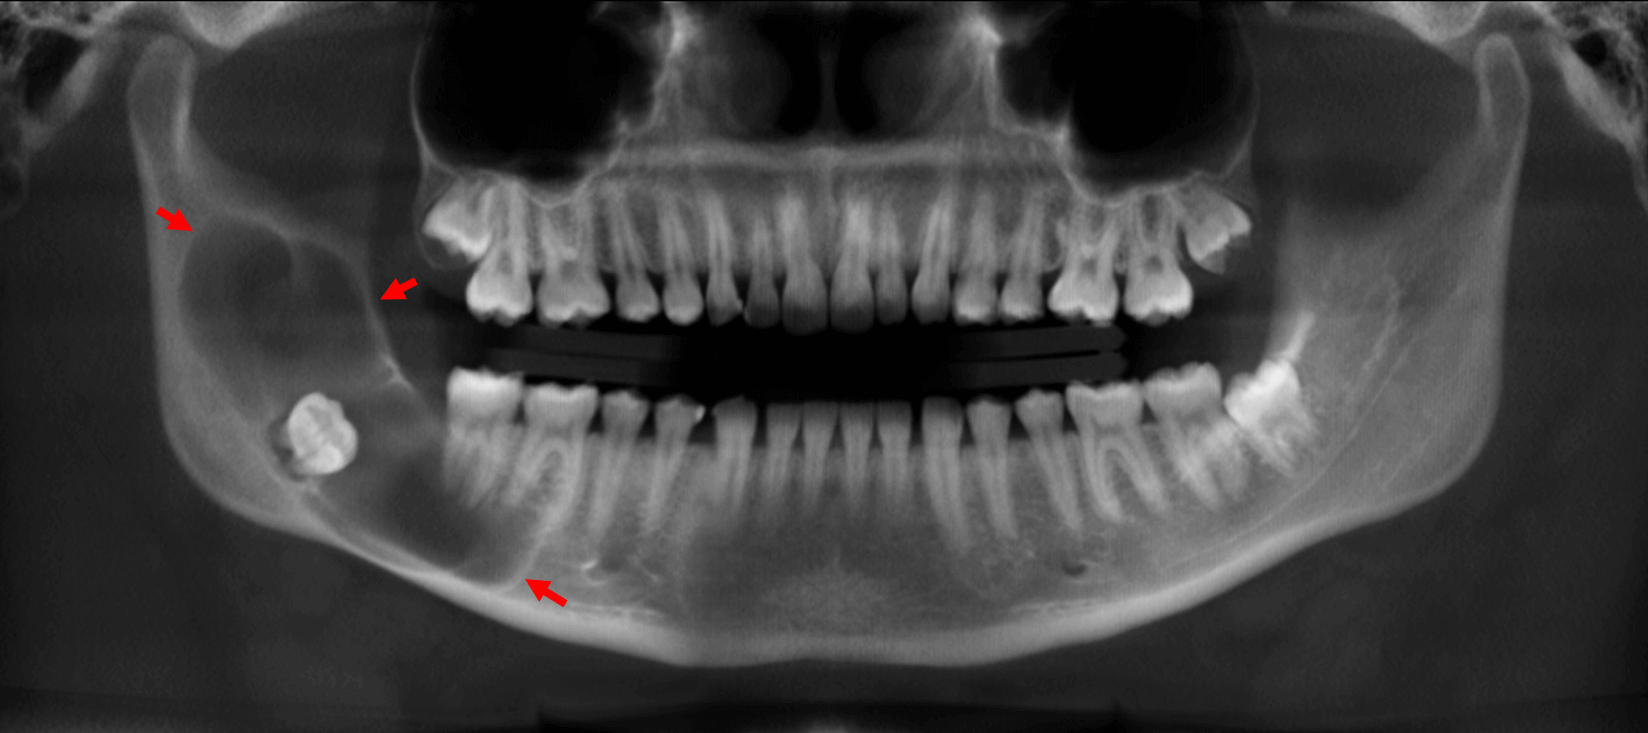

Fig.1

En la evaluación con tomografía computarizada cone beam, se observa en la reconstrucción panorámica (Fig.1) una lesion osteolítica que compromete el lado derecho de la mandíbula a nivel del cuerpo, ángulo y rama ascendente. Dicha lesion es unilocular y de limites definidos, y se extiende desde el cuerpo mandibular comprometiendo el soporte óseo del órgano dentario 46 y 47 y se extiende hasta el tercio superior de la rama ascendente. Nótese el órgano dentario 48 en proceso de evolución y en relación a la lesion osteolítica y desplazamiento hacia la rama mandibular.